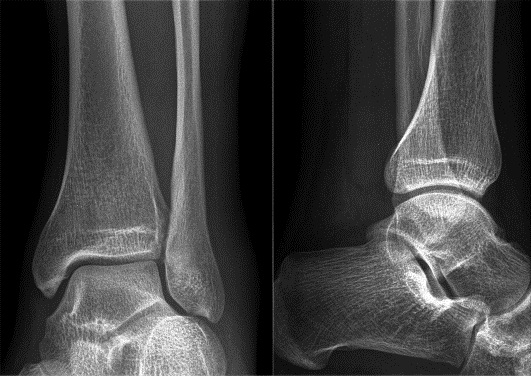

Запитання 56

СУГЛОБ УТВОРЕНИЙ СУГЛОБОВИМИ ПОВЕРХНЯМИ ЛАТЕРАЛЬНОЇ І МЕДІАЛЬНОЇ КІСТОЧКИ ТА ТІЛОМ ТАРАННОЇ КІСТКИ. РУХИ НАВКОЛО ФРОНТАЛЬНОЇ ОСІ. ЧАСТО - РОЗТЯЖІННЯ, ВИВИХИ, РОЗРИВИ, ПЕРЕЛОМИ. РОЗПІЗНАЙТЕ СУГЛОБ.

варіанти відповідей

КОЛІННИЙ С.

ГОМІЛКОВО-СТОПНИЙ С.

КУЛЬШОВИЙ С.

ЛІКТЬОВИЙ С.

ПЛЕЧОВИЙ С.

ПРОМЕНЕВО-ЗАП'ЯСТКОВИЙ С.

СКЛАДНИЙ СУГЛОБ (ЯК ВИЛКА). Є ВСІ ПЕРЕДУМОВИ ДЛЯ РОЗТЯГНЕННЯ ЗВ'ЯЗОК І ЗМІЩЕННЯ КІСТОК. РОЗПІЗНАЙТЕ СУГЛОБ.